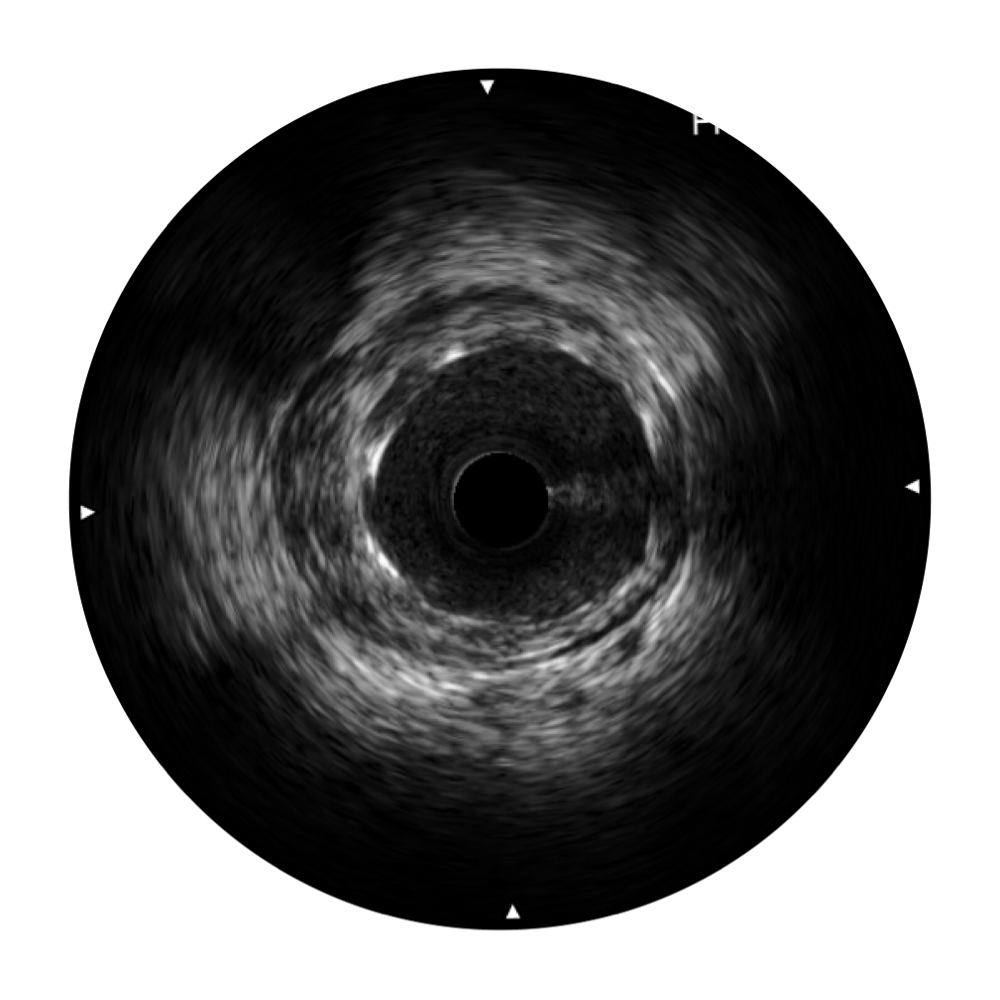

1xBET宽频IVUS图像

对比传统IVUS导管成像,1xBET宽频IVUS图像的近场支架梁显影更细腻,远场中膜外血管仍清晰可辨,兼顾远中近,兼顾分辨力与穿透深度